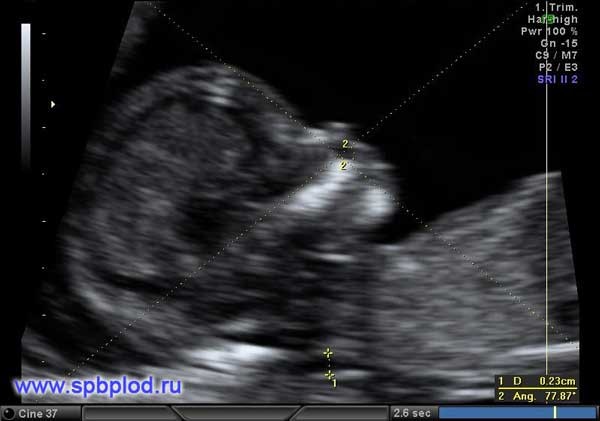

Для оценки этих признаков врач должен обладать высокой квалификацией, так как получение необходимых ракурсов плода в ранние сроки беременности требует опыта и технических навыков. Для измерения ТВП необходимо получить такое изображение:

На фото УЗИ беременной видна только голова и верхняя часть туловища плода, четко виден профиль, носовая кость и ТВП. Достаточно часто можно увидеть такие некорректные изображения:

На этих изображениях плод лежит криво, увеличение изображения недостаточное, нельзя увидеть четкий профиль плода. Измерение ТВП в таких изображениях НЕКОРРЕКТНО и приводит к завышению или занижению риска болезни Дауна!!!

Методика измерения лицевого угла плода в 12 недель беременности